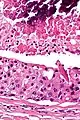

| Low magnification micrograph of a salivary duct carcinoma with characteristic comedonecrosis (left of image) adjacent to normal parotid gland (right of image). H&E stain. | |

Their histologic appearance is similar to ductal breast carcinoma.

Very low mag.